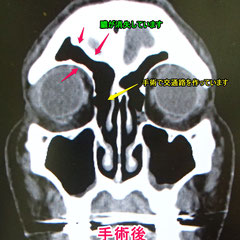

この患者さんは、右眼の上の持続的な痛みで受診された方です。

頬や目の内側、奥、おでこの部分に4つの副鼻腔という空洞があります(→副鼻腔炎とは)

この方は前頭洞という前額部の奥の空洞とお鼻の間の交通路がつまっており、前頭洞の中に膿がたまった前頭洞炎を起こしていました。

こういう嚢腫は、手術で鼻腔側から交通をつけます。